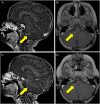

Methods: Patients with recurrent or progressive ATRT received alisertib 80 mg/m(2) by mouth once daily for 7 days of a 21-day treatment cycle. Disease evaluation (MRI of brain and spine and lumbar puncture) was done after 2 cycles of alisertib and every 2-3 cycles thereafter for as long as the patients remained free from tumor progression.

Results: Four patients with median age of 2.5 years (range, 1.39-4.87 y) at diagnosis received alisertib 80 mg/m(2) by mouth once daily for 7 days of a 21-day treatment cycle, and all 4 patients had disease stabilization and/or regression after 3 cycles of alisertib therapy. Two patients continued to have stable disease regression for 1 and 2 years, respectively, on therapy.

Conclusions: Single-agent alisertib produced marked and durable regression in disease burden, as detected by brain and spine MRI and by evaluation of spinal fluid cytology. Alisertib has moderate but manageable toxicities, and its chronic administration appears feasible in this pediatric population. These novel data support the incorporation of alisertib in future therapeutic trials for children with ATRT.